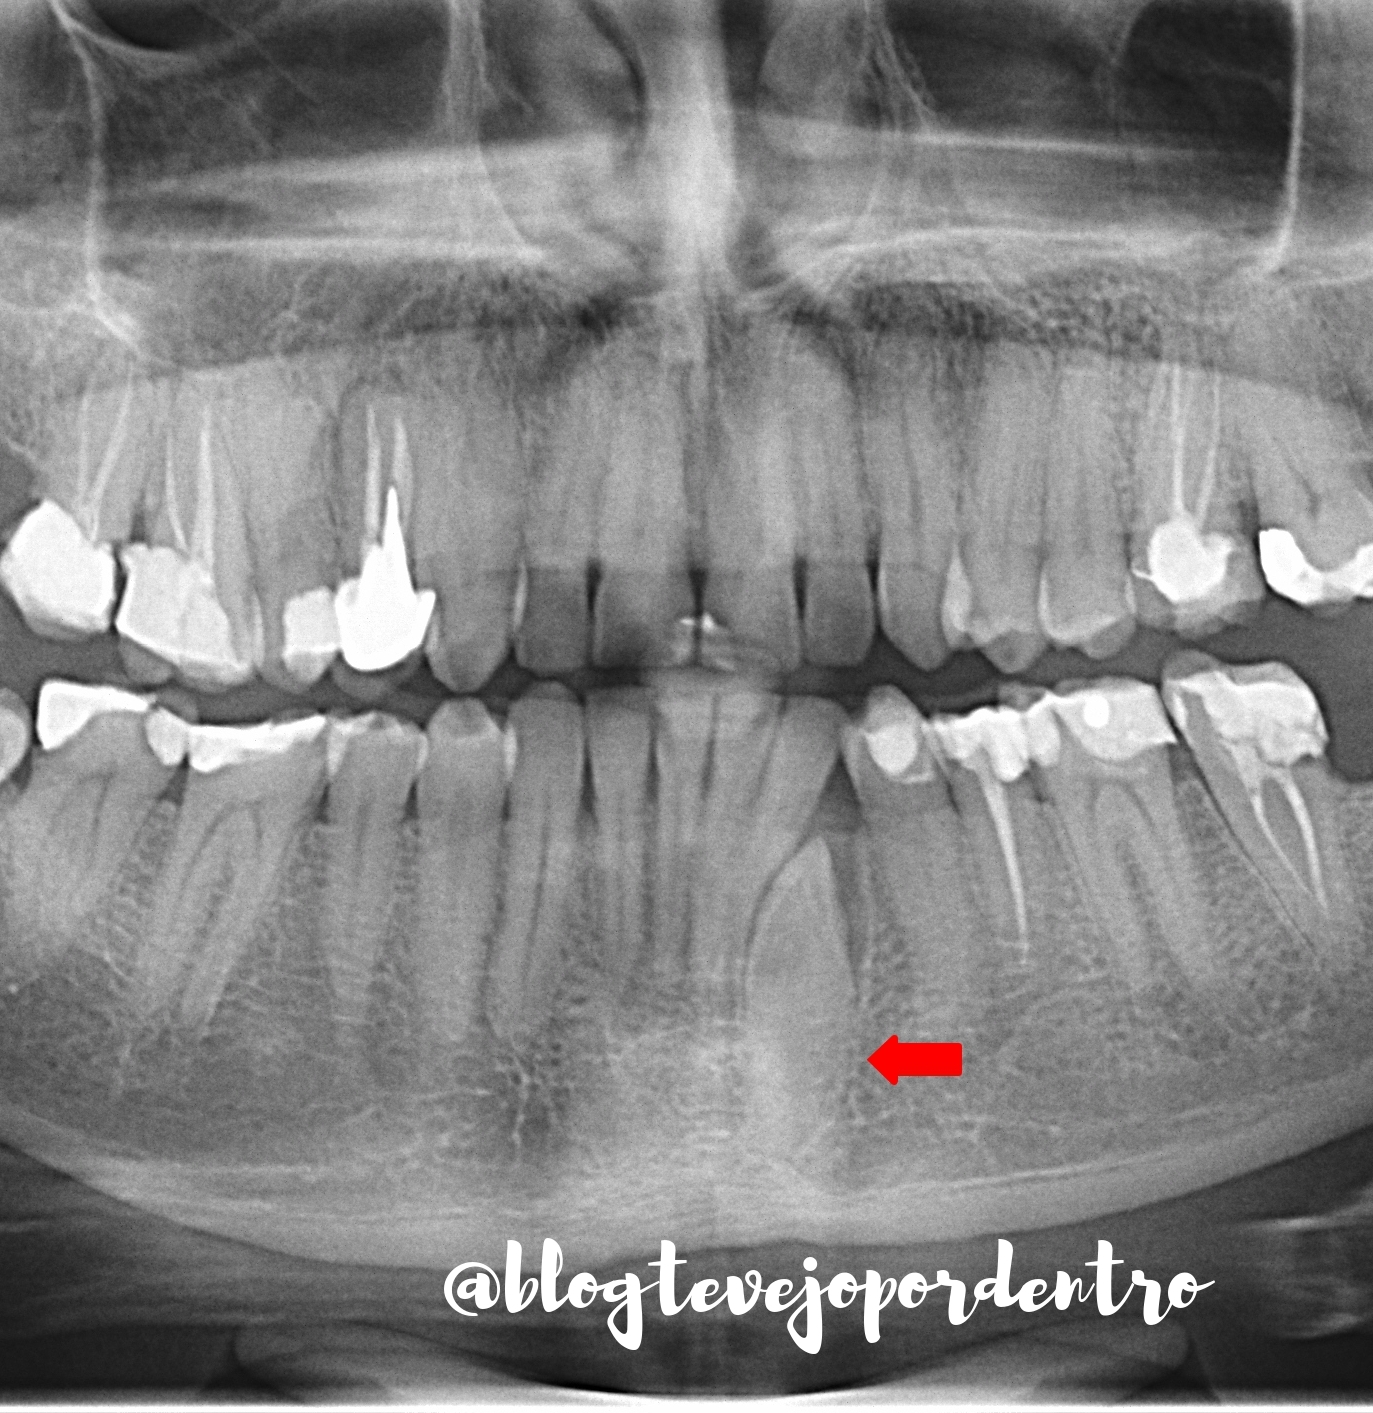

Imagem Radiográfico da Semana (148)

Neste recorte de radiografia panorâmica destaco dente 33 incluso.